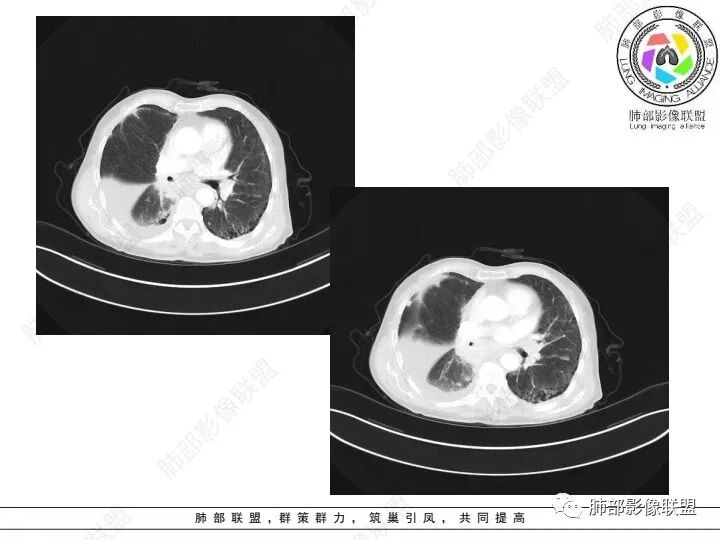

精彩讨论

宇宙:

右肺下叶胸膜下不规则肿块,与肺门相连,不均匀强化,胸壁受侵,右肺内多发小结节,下叶血管束增粗,小叶间隔增厚,右肺门及纵膈多发淋肿大淋巴结,融合,右侧胸水,考虑腺癌转移

患者老年女性,腹痛、黑便4小时。查肿瘤结果CA125明显升高,余正常。胸部CT:双肺胸膜下间质性改变,右肺胸膜下多发结节灶,以右肺下叶为大,增强渐进性强化,内低密度灶。右肺门淋巴结肿大伴钙化,右中间支气管狭窄,右侧包裹性胸腔积液。综合考虑恶性,腺癌可能大。鉴别转移。

1、老年男性,腹痛、便血就诊,既往有甲减病史,其余病史无特殊。

2、实验室检查CA125明显升高,其余肿瘤标志物无异常。

3、胸部增强CT示右肺下叶脊柱旁不规则软组织肿块,侵及壁层胸膜外,密度不均匀,不均匀强化,中心低密区可疑坏死,右侧胸腔积液、胸膜结节影或结节样增厚,增强扫描可见强化,右侧肺门及纵隔内可见淋巴结肿大、融合,右侧中尖段支气管及右肺下叶支气管受侵,管腔狭窄。

4、综上,老年男性,CA125升高,右肺下叶肿块侵犯胸壁,伴纵隔、右肺门及纵隔淋巴结肿大,右侧胸腔积液、胸膜增厚伴结节影,强化明显,应该为一较典型的肺癌伴肺胸膜腔及肺门纵隔淋巴结转移,尤其是肺腺癌。